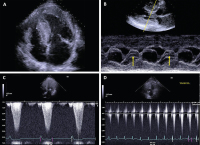

Echo - HCM

Abbildung 2: Echokardiographie bei HOCM. (A): Reverse-curve-Phänotyp („Zipfelmützen“-artige Kontur) des linken Ventrikels, (B): SAM-Phänomen der Mitralklappe, Darstellung im M-Mode (Pfeile), (C): LVOT-Ruhe-Gradient, (D): Anstieg des LVOT-Gradienten unter Valsalva-Manöver.